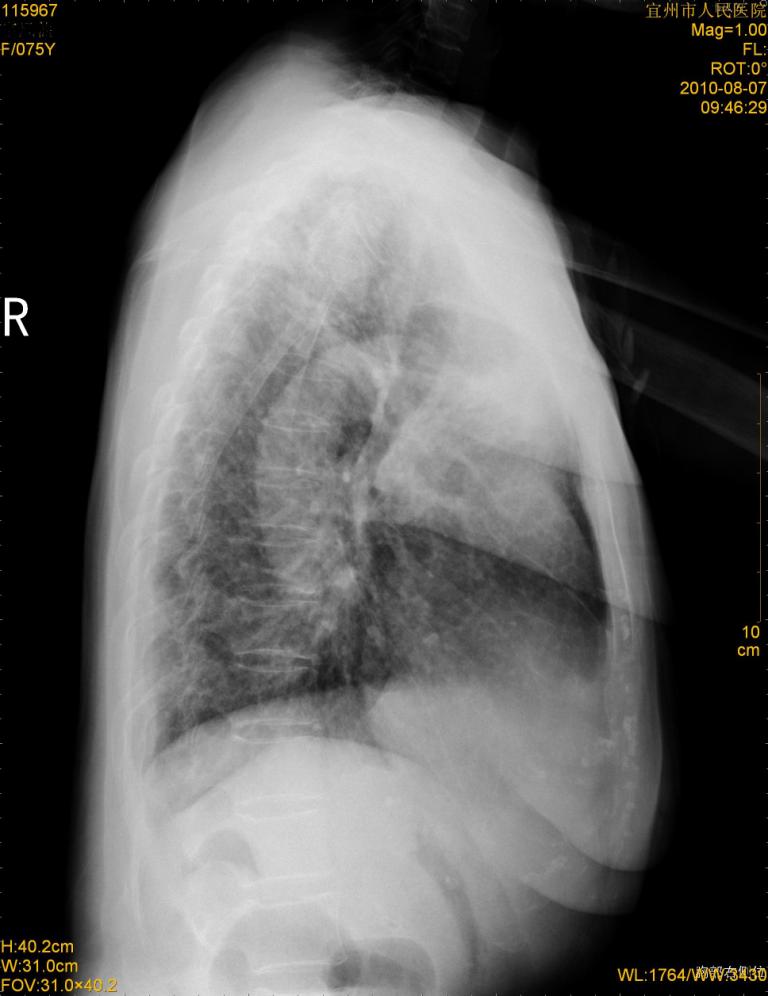

标题: CT28313:两肺弥漫性病变

女,75岁,患者反复头昏乏力面色苍白3年,再发10天入院。临床贫血查因。

双肺间质增生并右肺上叶炎性改变,不除外右肺上叶结核病肺内播散

考虑右肺上叶炎症合并双肺结核可能性大,建议上传纵隔窗ct图片。

双肺结核可能性大

考虑尘肺并结核;右上肺支气管扩张!

结核、尘肺、支气管肺泡癌都不能除外

右肺上叶继发性肺结核伴肺内血型播散!

考虑右肺上叶继发性肺结核伴两肺播散。